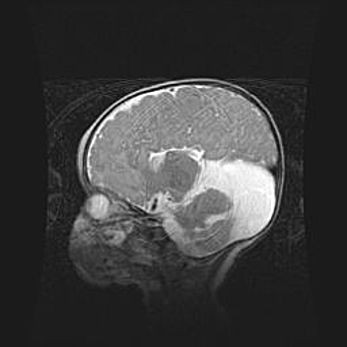

Аномалия Денди-Уокера. Признаки гипоплазии мозолистого тела.

Возраст: 5 месяцев 3 дня

Вес: 5550 г

Пол: мужской

Окружность головы: 39 см

Срок гестации: 40 недель

Аномалия Денди-Уокера – это порок развития головного мозга, для которого характерна триада симптомов: гипотрофия или аплазия червя мозжечка и/или полушарий мозжечка, расширение четвёртого желудочка с формированием ликворной кисты задней черепной ямки, гипертензионная гидроцефалия различной степени.

Гипоплазия мозолистого тела относится к дефектам внутриутробного этапа развития мозговой ткани, возникающим в процессе закладки структур головного мозга, что происходит на начальных этапах развития эмбриона.